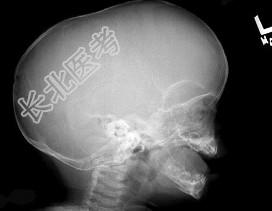

- 单项选择题男婴,10个月, 头颅畸形,分离性斜视, 见X线平片所示,最可能诊断是 ( )

A、显性颅裂

B、狭颅征

C、先天性脑积水

D、颅底陷入症

E、以上均不对